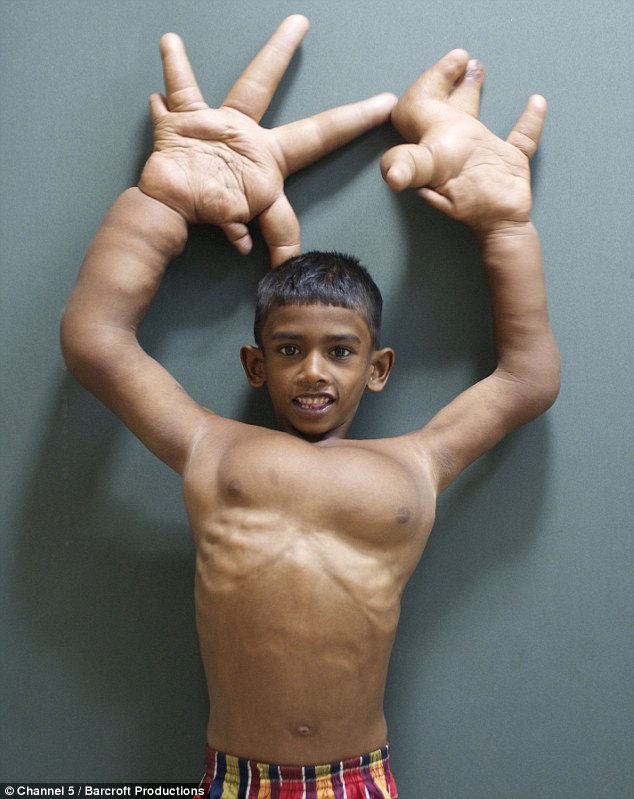

Un niño de 8 años que sufría gigantismo fue sometido a una intervención quirúrgica bastante complicada.

Su nombre es Mohammad Kaleem, este pequeño vive en la India y el problema es que sus manos y sus brazos crecieron sin control. Desafortunadamente ha tenido que vivir mucha discriminación por parte de sus compañeros de escuela y también por las autoridades, ya que los directivos argumentan que sus manos podrían asustar a otros niños.

También ha sido discriminado por los vecinos de su comunidad pues creen que sus manos son una maldición y lo nombran “el hijo del diablo”. Las manos de Kaleem no le permiten realizar ciertas actividades básicas cómo vestirse o comer, además sus padres no cuentan con una economía estable por lo que no pueden darle todos los cuidados médicos que necesita.

Afortunadamente varios médicos del sur de la India se interesaron en el caso de este niño. Los padres recibieron esta noticia con mucha emoción pues ellos ya habían pensado que tendrían que acostumbrarse a su difícil modo de vida.

Se trató de una operación muy complicada ya que el objetivo era reducir el tamaño de los dedos y de las manos sin dañar ninguno de sus nervios. Los especialistas mencionaron al respecto:

La operación duró cerca de 8 horas, después este chico tenía que someterse a otras cirugías para que sus manos y dedos no crecieran más. No obstante de los resultados la gente del pueblo seguía pensando que el niño estaba maldito. Uno de los aldeanos mencionó:

Las operaciones han tenido éxito pero aún falta mucho para obtener mejores resultados. Su familia está dispuesta a seguir apoyándolo para que tenga otras intervenciones médicas que ayuden a que tenga una mejor calidad de vida.